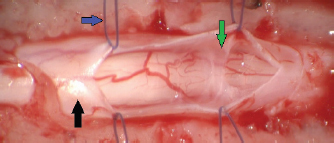

The following data were recorded for each dog: signalment, clinical history, clinical and neurological examinations, magnetic resonance imaging (MRI) findings, confirmed diagnosis after surgical exploration, standardized surgical procedure, and outcome at least 6 months after surgery. Dogs were anaesthetized according to the standard ethics procedure using anesthetic medications. MRI of the spinal cord was acquired under general anesthesia in dorsal recumbency using low-field MRI scanners (Hitachi aperto grande 0.4T; Esaote Vet Grande, Genova, Italy). Interpretation of the images was obtained in seven dogs by a board-certified radiologist and in one dog by a neurology clinician. All spinal surgeries were performed using a surgical microscope (Zeiss NC-2). A dorsal laminectomy approach was taken in all cases by removing the dorsal lamina over the SAD and preserving the articular facets joints (Funkquest, type B). This approach permitted a good visualization of the dorsal spinal cord, allowing the performance of a longitudinal durotomy with a no. 11 blade and microsurgical Castroviejo scissors (Fig. 1). The durotomy was extended cranially and caudally to the SAD until normal spinal cord was exposed. Stay sutures were then applied at the dural edges and maintained in place with small hemostats using a polydioxanone 6-0 (Ethicon LLC, San Lorenzo, PR) (Fig. 2). This technique exposed the SAD allowing the visualization of the subarachnoid diverticulum, subarachnoid CSF accumulation, and surrounding adhesions, most of which were microsurgically removed (Figs. 35). The stay sutures were not used for dural closure, and the holes of the stay sutures were incorporated into the durotomy repair. In all cases, the dural closure was completed using a simple continuous pattern with polydioxanone 6-0 (Ethicon LLC, San Lorenzo, PR) in seven dogs and with polyamide 5-0 (Ethicon LLC, San Lorenzo, PR) in one dog; waterproof suture was achieved by noting the absence of CSF leakage (Fig. 6). No dural patch or autologous material was placed over the laminectomy defect. The muscular, subcutaneous, and skin layers were routinely closed. The Glasgow modified pain score system was utilized for the postoperative provision of analgesia. Dogs were hospitalized until good pain management was achieved with oral medication and satisfactory movements of pelvic limbs were observed. Outcome was deemed unsuccessful if there was progressive neurological deterioration and successful if the neurological signs were similar or improved compared to the neurological signs at presentation. Short-term and long-term outcomes were defined as less than 7 months and more than 7 months. Follow-ups were evaluated by neurological examination by the authors in the same institution where the spinal surgery was performed or by custom-designed telephone questionnaire used by Alisauskaite et al. (2019), along with a video evaluation of the dog sent via email from the owner. In addition, owner’s level of satisfaction regarding the neurological improvement was recorded.

Fig. 1. Spinal cord (black arrow) after longitudinal durotomy and adherences exposure (green arrow) via stay suture (blue arrow).